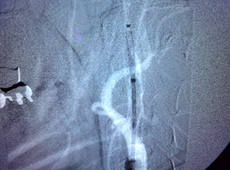

1ヶ月の研修で、脳血管撮影や開閉頭の助手、穿頭術などを一通り経験できます。2ヶ月以上の研修であれば、指導医のもと慢性硬膜下血腫小手術などの術者になることも可能です。